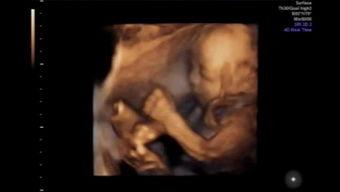

你有没有想过,如果宝宝的视频能跳出平面,变成一个立体的世界,那会是怎样的景象呢?想象宝宝的每一个微笑、每一个动作都能在你的眼前栩栩如生地展现,这就是四维视频宝宝动态视频的魅力所在。今天,就让我带你一起探索这个神奇的世界,看看它如何让宝宝的成长记录变得更加生动有趣。

首先,得先弄清楚什么是四维视频。四维视频,顾名思义,是在传统的三维视频基础上,加入了时间维度,使得视频内容更加丰富、立体。而宝宝动态视频,则是专门针对宝宝成长过程录制的视频,通过四维技术,让这些视频变得更加生动。

1. 立体感强:传统的视频只能展现宝宝的平面形象,而四维视频则能将宝宝的每一个动作、每一个表情都立体地呈现在你面前,仿佛宝宝就在你眼前。